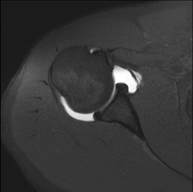

- RM d'Espatlla

Exploració per a l'estudi de lesions en els tendons, els músculs i les articulacions. La seva principal utilitat resideix en diagnosticar les lesions dels tendons del braçal rotatori. Té una durada aproximada de 20 minuts. No utilitza radiació ionitzant. - RM de Braç

Exploració per a l'estudi de les lesions en petites estructures anatòmiques de l'articulació que solen lesionar-se en pacients que pateixen luxació o inestabilitat crònica. L'estudi ve precedit per una injecció de contrast a l'interior de l'articulació, realitzada sota control de raigs X. La durada total dels dos procediments és de 50 minuts. - Artro-RM de Canell